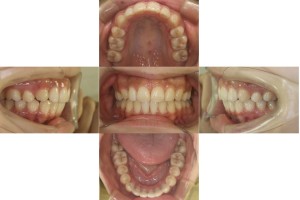

上顎の傾斜と下顎のがたつきが取れ、綺麗な噛み合わせになりました。

| 年齢層 | 20代 |

| 性別 | 女性 |

| 主訴 | 出っ歯を改善したい |

| 治療費用 | 1,397,000円 |

| 治療期間 | 1年4ヵ月 |

| 抜歯 | 上顎両側4番 |

| 矯正の装置 | リンガル(上下裏側装置) |

| 副作用、リスク | 歯肉退縮,歯根吸収,疼痛,咬合の違和感,装置の違和感,虫歯,歯肉炎 |